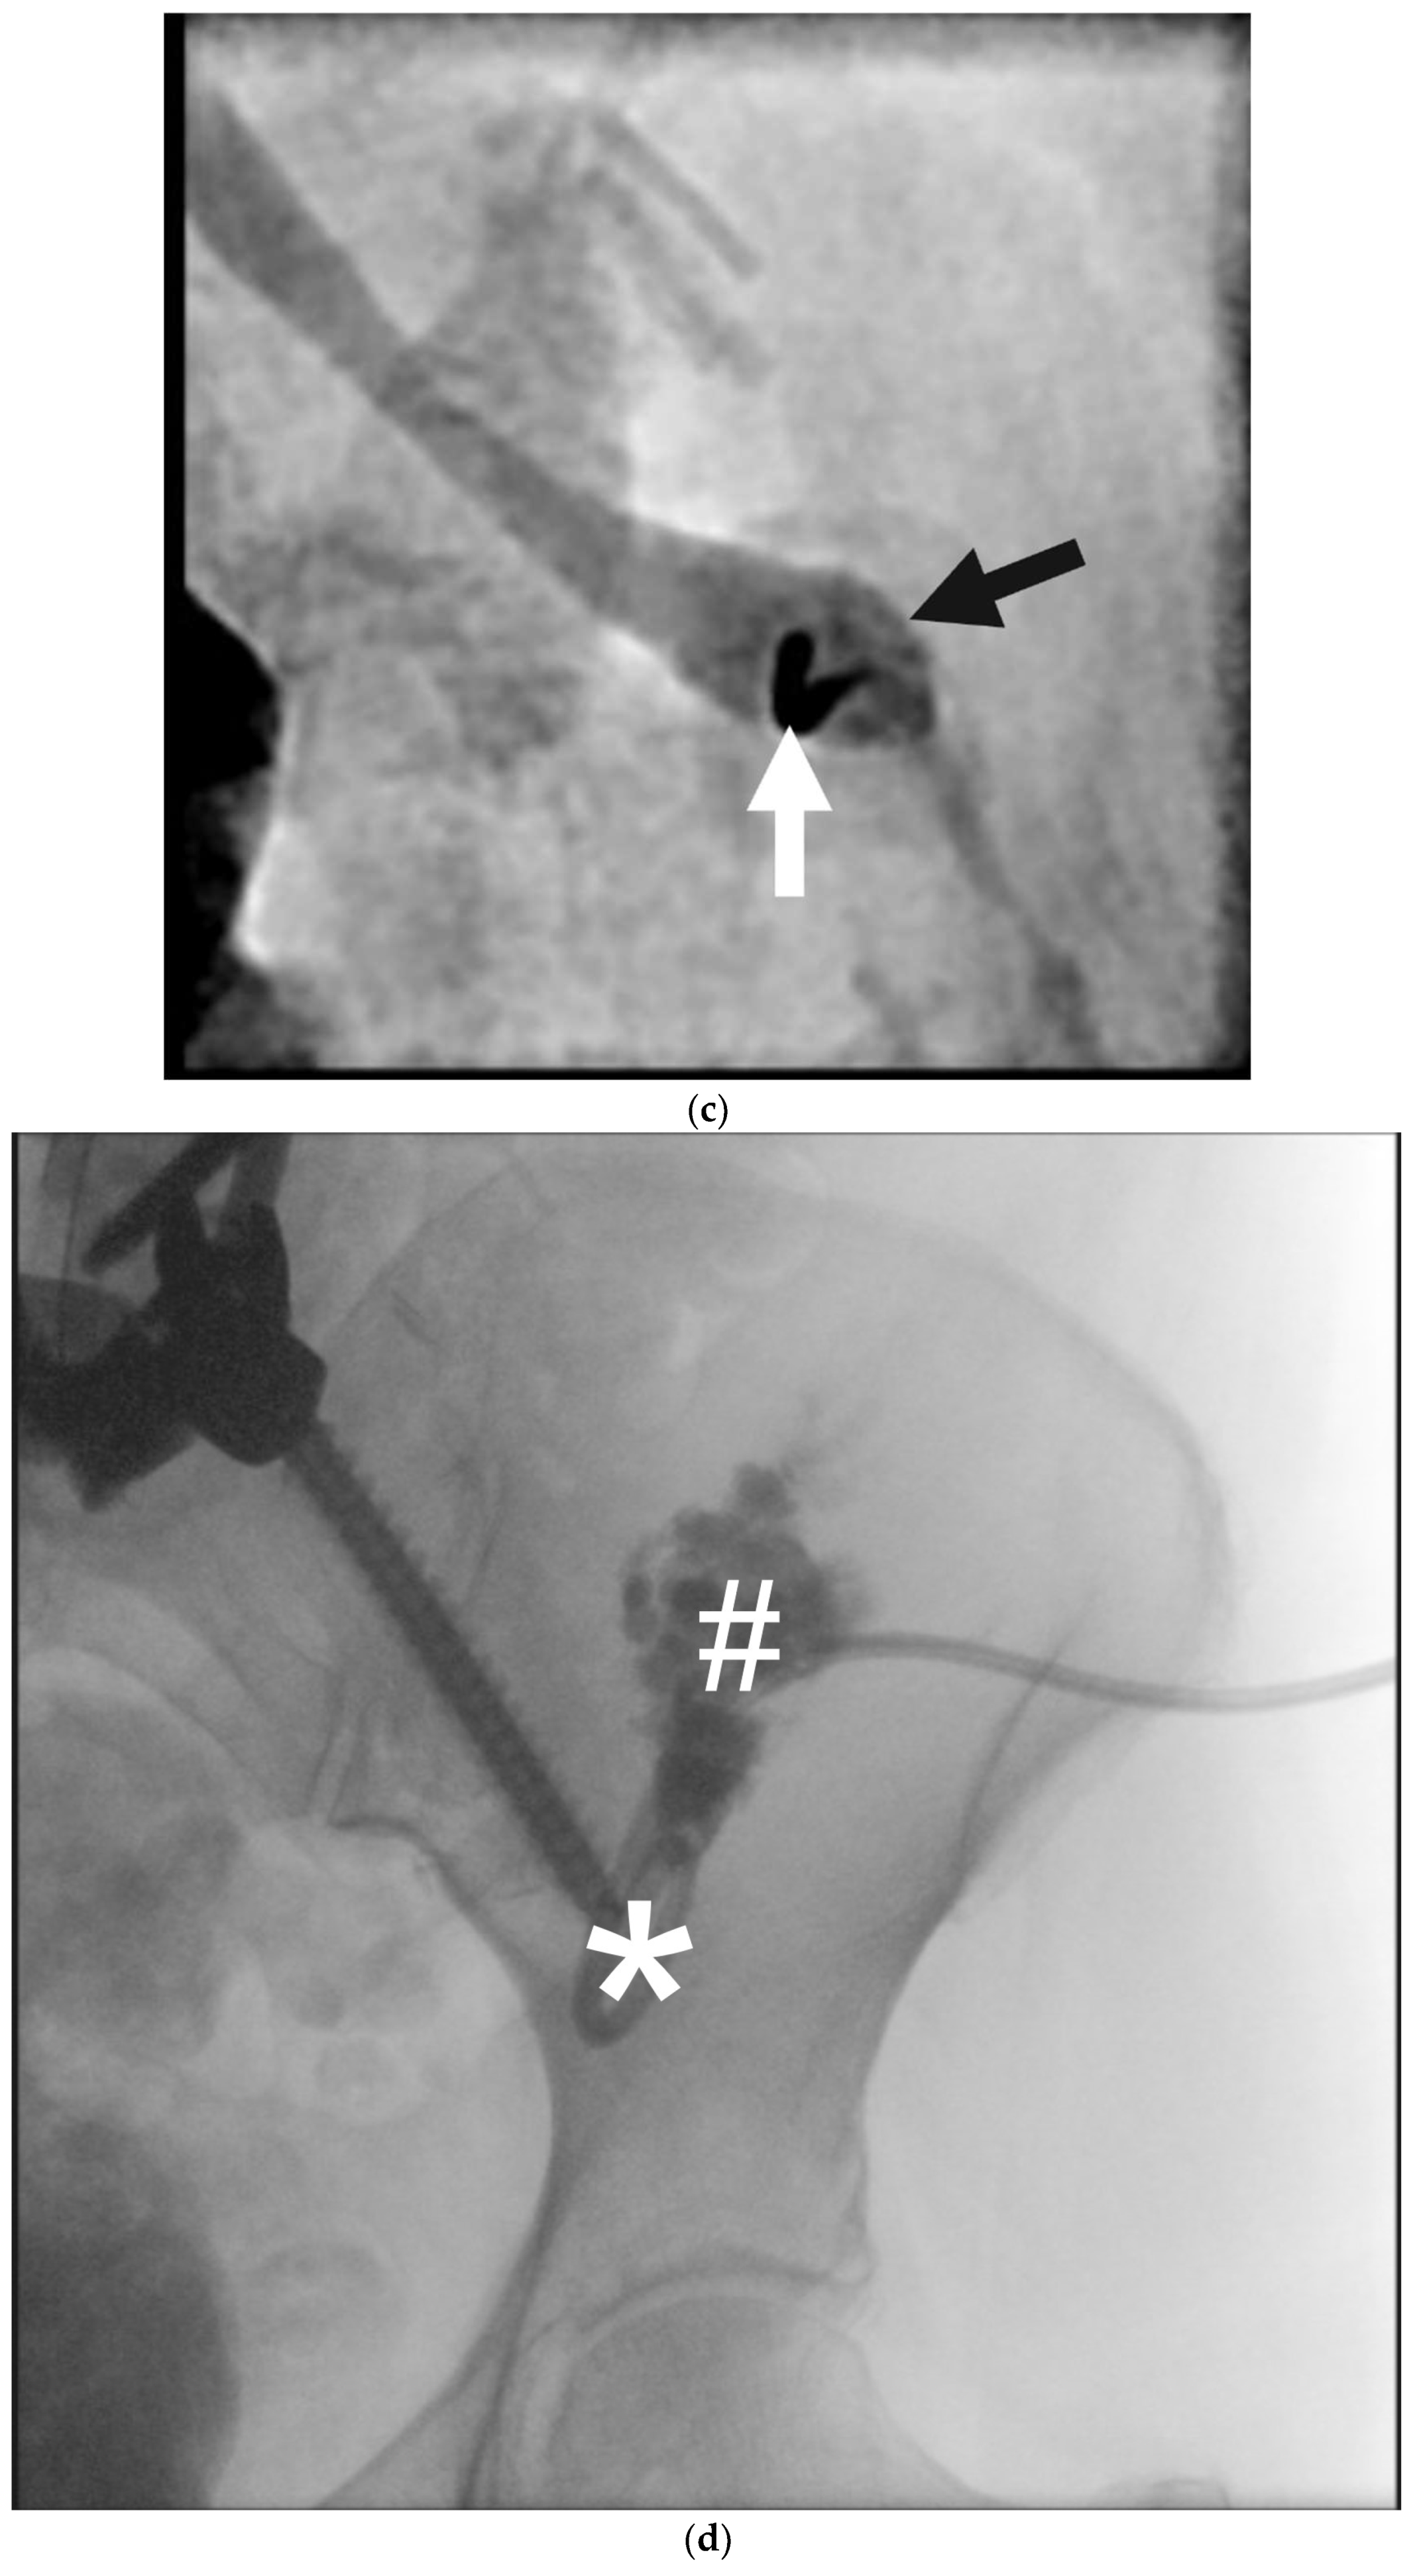

Figure 8. Thoracic duct embolization for chylothorax in a 54-year-old man after bilateral lung transplantation. (a) The white arrow indicates a 22G needle that has successfully punctured the cisterna chyli (*). The black arrow indicates a guidewire, inserted through the needle and used to catheterize the thoracic duct. The wire should track without resistance, indicating its location in a hollow tube. (b) Thoracic duct lymphangiogram. Water-soluble contrast is injected under digital subtracted angiography. The white arrow identifies the normal left-sided thoracic duct terminus. The black arrows show abnormal collateral drainage pathways to the right hemithorax, which are abnormal and contributory to chylothorax. A large leak (*) in the right chest is identified as the source of chylothorax. (c) The black arrow indicates the location of radio-opaque metallic coils used to embolize the thoracic duct terminus. This is performed to prevent liquid nBCA glue embolic from draining to the vein and embolizing to the lungs. The white bracket shows an opacified thoracic duct with glue, embolized in a 1:1 mixture of nBCA glue to ethiodized oil. The glue mixture is injected under real-time fluoroscopy and watched as the catheter is slowly retracted, and then promptly removed.